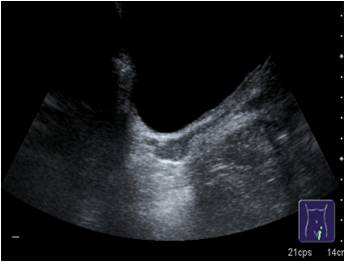

Lo primero y más importante, para atender convenientemente una petición de estudio de la Próstata lo que tenemos que tener es una vejiga lo suficientemente llena para poder valorarla bien. Una vejiga mal repleccionada puede darnos problemas, pero una vejiga excesivamente repleccionada, también, el paciente puede estar incómodo y sobre todo, una replección excesiva puede comprimir la glándula y desplazarla y no podremos estudiarla bien.

En ocasiones deberemos pedir al paciente que beba agua y no orine para poder realizar el estudio correctamente.

Al rellenar la Vejiga, lo que conseguimos es una «ventana» para visualizar mejor estructuras como las Próstata que están muy escondidas, por profundidad o por colocación Anatómica. Por eso es indispensable una buena preparación del paciente. Se consigue gracias al aumento de transmisión favorecido por espacios puramente acuosos, como la vejiga llena de orina La interacción del haz ultrasónico y la materia lo explica bien.

Además de una vejiga suficientemente repleccionada, necesitamos esquivar el Pubis, anterior a la Próstata, para eso tendremos que realizar una angulación, que estará en función de cada paciente, para poder acceder a la glándula correctamente tanto en transverso como en longitudinal, que son los dos planos que necesitamos para hacer la medida de la Próstata en los tres ejes de espacio para obtener un volumen de la estructura.

Para llegar a ver la Próstata, con el paciente debidamente preparado, vamos a localizar un corte transverso de la Vejiga y cuando la veamos, realizaremos la angulación arriba mencionada para llegar a la Próstata, este paso es el más complicado técnicamente, pero aquí reside el éxito de la exploración, mira, he hecho un dibujo para explicarlo:

Corte localizador Vejiga.

Resultado.

Con angulación caudal.